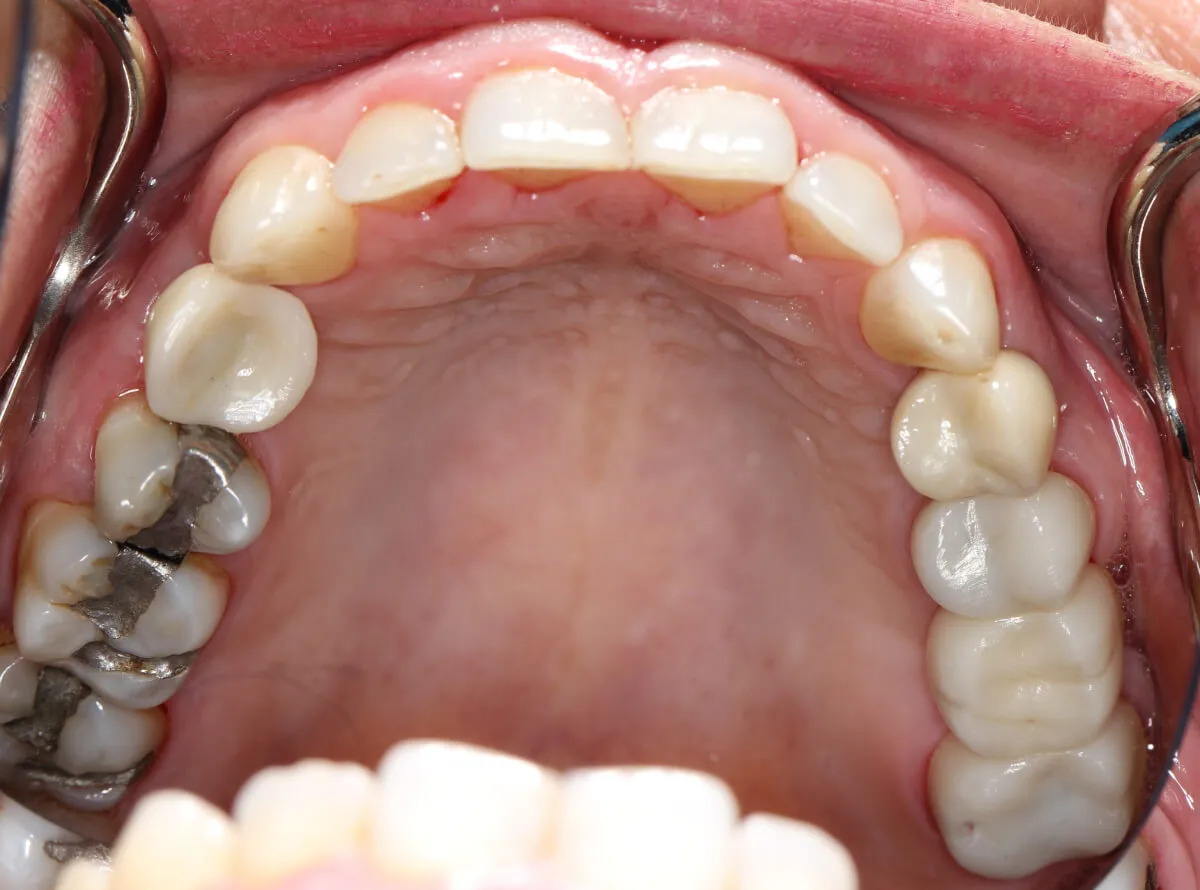

This lady received two dental implants and a bridge to replace her upper missing teeth. We restored her teeth, smile and boosted her confidence. She is very happy with the results and smiles with higher confidence.